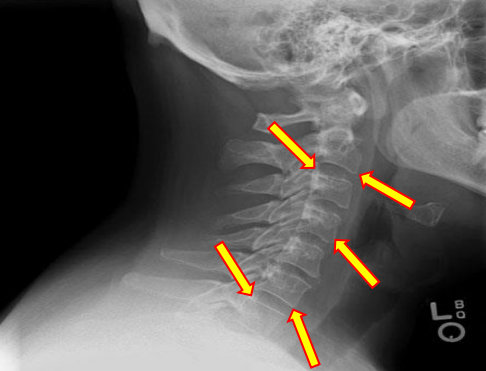

Uncinate processes

Inferior aspect of vertebral bodies

Junction of laminae

Pedicle shadows

Vertebral waist

Inferior endplate tips

Superior endplate tips

Disc spaces

End plate tips